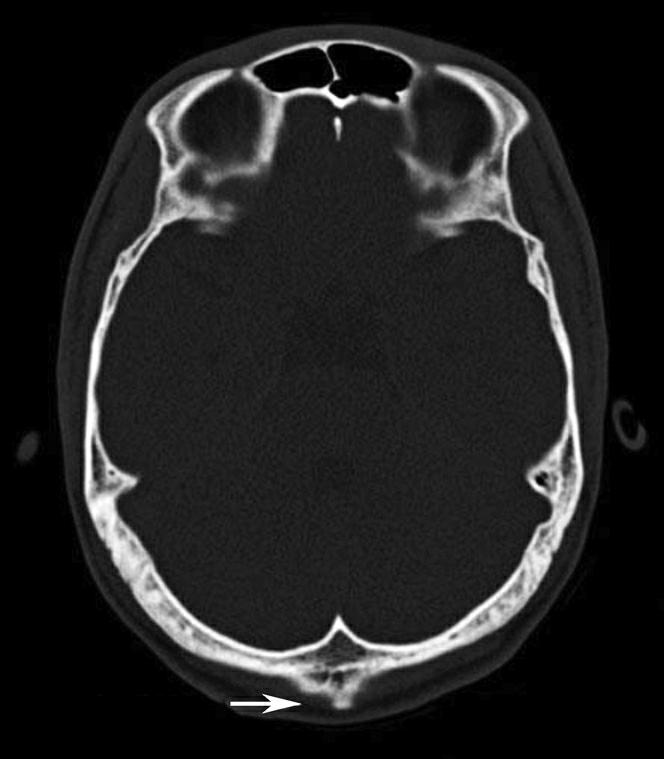

破裂孔、卵圆孔、棘孔及斜坡等均为重要的解剖结构,临床常见疾病如鼻咽癌常侵犯上述结构(图1-2-3)。颈静脉孔区较常见的肿瘤为颈静脉球瘤,常伴有颈静脉孔及其邻近骨质的破坏(图1-2-4)。

图1-2-4 右侧颈静脉球瘤

A.横断面(骨窗);B.横断面

右侧颈静脉孔区不规则骨质破坏(箭),局部见软组织肿块(☆)